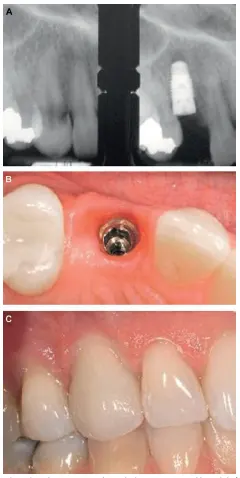

شکل VII‑8. جایگزینی دندان منفرد

A) رادیوگرافی قبل و بعد از کشیدن با ایمپلنت در محل

B) ایمپلنت آماده‌ی بازسازی پس از ترمیم

C) نتیجهٔ نهایی

شکل VII‑8 (ادامه)

شکل VII‑8 (ادامه): رادیوگرافی نهایی D